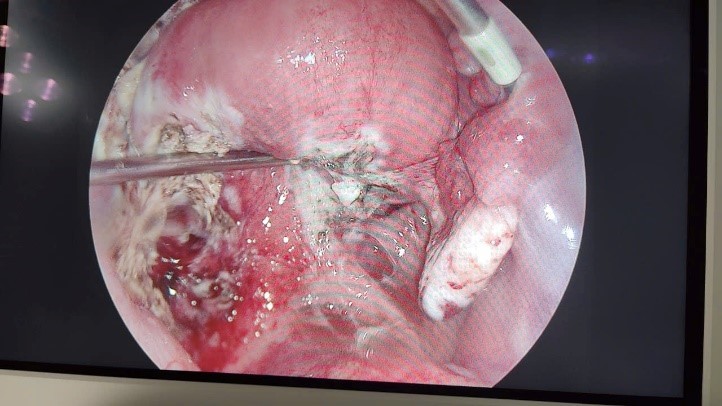

![]() |

Hình ảnh trước và sau phẫu thuật khối u buồng trứng